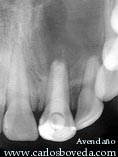

En esta radiografía periapical, puede observase el tratamiento endodóntico defectuoso a nivel del 21, el cual además presenta ápice inmaduro y una restauración coronal defectuosa. Se observa además en detalle la imagen radiolúcida apical en relación con los ápices dentarios.